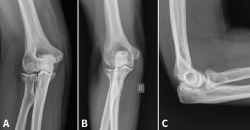

Figura 2. Ejemplo de fractura de Mason II tratada de forma conservadora. A: proyección anteroposterior (AP) aguda; B y C: AP y lateral a los 6 meses.

Las fracturas que afecten a menos de un tercio de la cabeza radial y que no produzcan bloqueo de la articulación podrían tratarse de igual modo que las de tipo I con buenos resultados a largo plazo. Inestabilidad y desplazamiento no son sinónimos. Incluso con un desplazamiento de más de 2 mm o con más de un fragmento, hay fracturas que siguen siendo estables gracias a que las estructuras periósticas están preservadas; por tanto, no son indicación absoluta de tratamiento quirúrgico (Figura 2)(11,12).